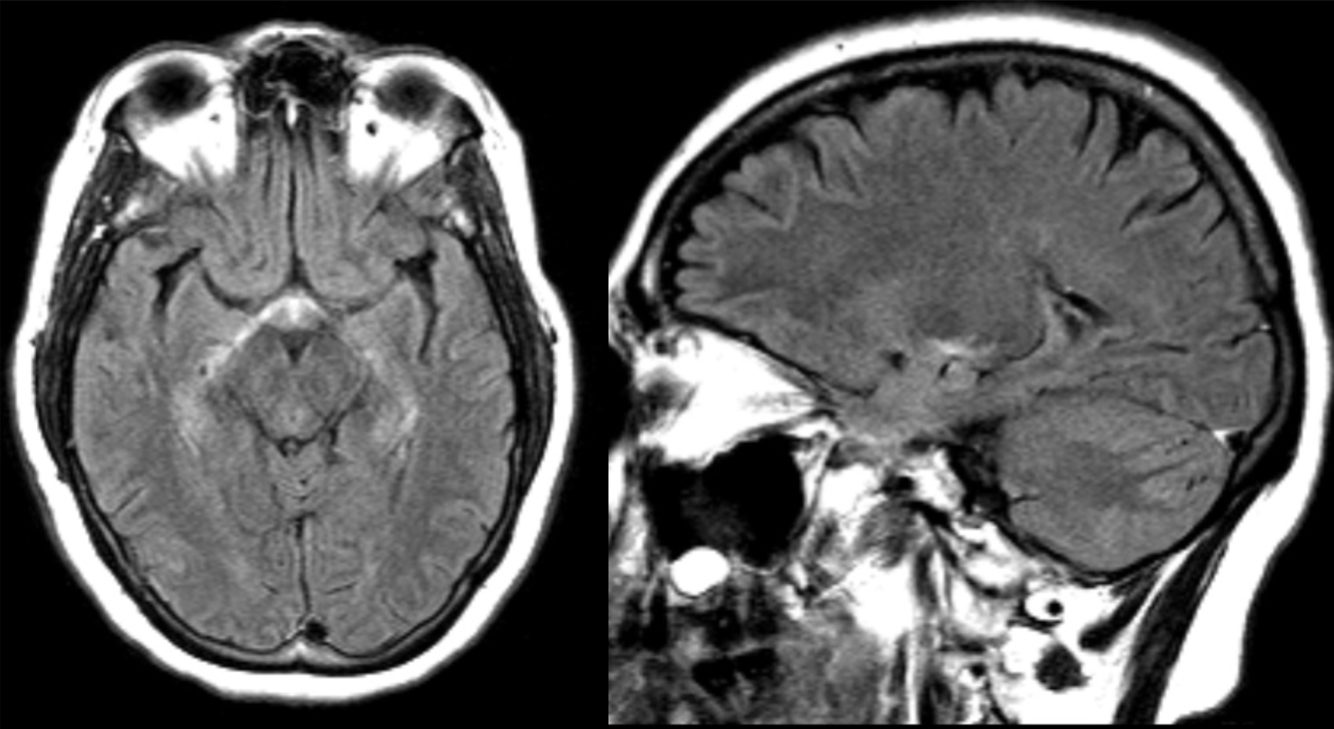

A 30 year-old female presented with with double vision.

Multiple sclersois - Dawson’s fingers

Multiple sclerosis - Juxtacortical lesions

Multiple sclerosis - infratentorial lesions

Multiple sclerosis - lesions in corpus callosum